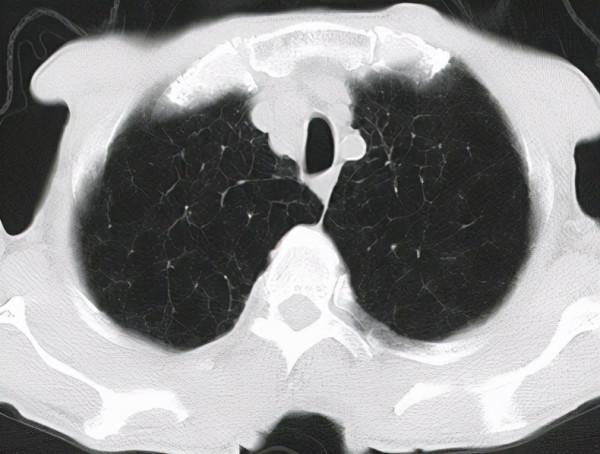

秋末入冬之際,與一位72歲高齡的慢阻肺患者進行了遠端看診。此前,患者的家屬一直在頭條平臺上看我的科普內容和病例分享,後來有一天找我,明確表示想讓我給他父親看看病。據瞭解,患者已經反覆的咳嗽、咳痰20多年,當時痰液白色的,比較少,發作的時間常在冬春季,因為自己不夠重視,以為小感冒,沒有到醫院看過。在10年前一次外出旅遊過程中出現了氣喘,咳嗽、咳痰和之前相比更加嚴重,送醫確診為慢阻肺。